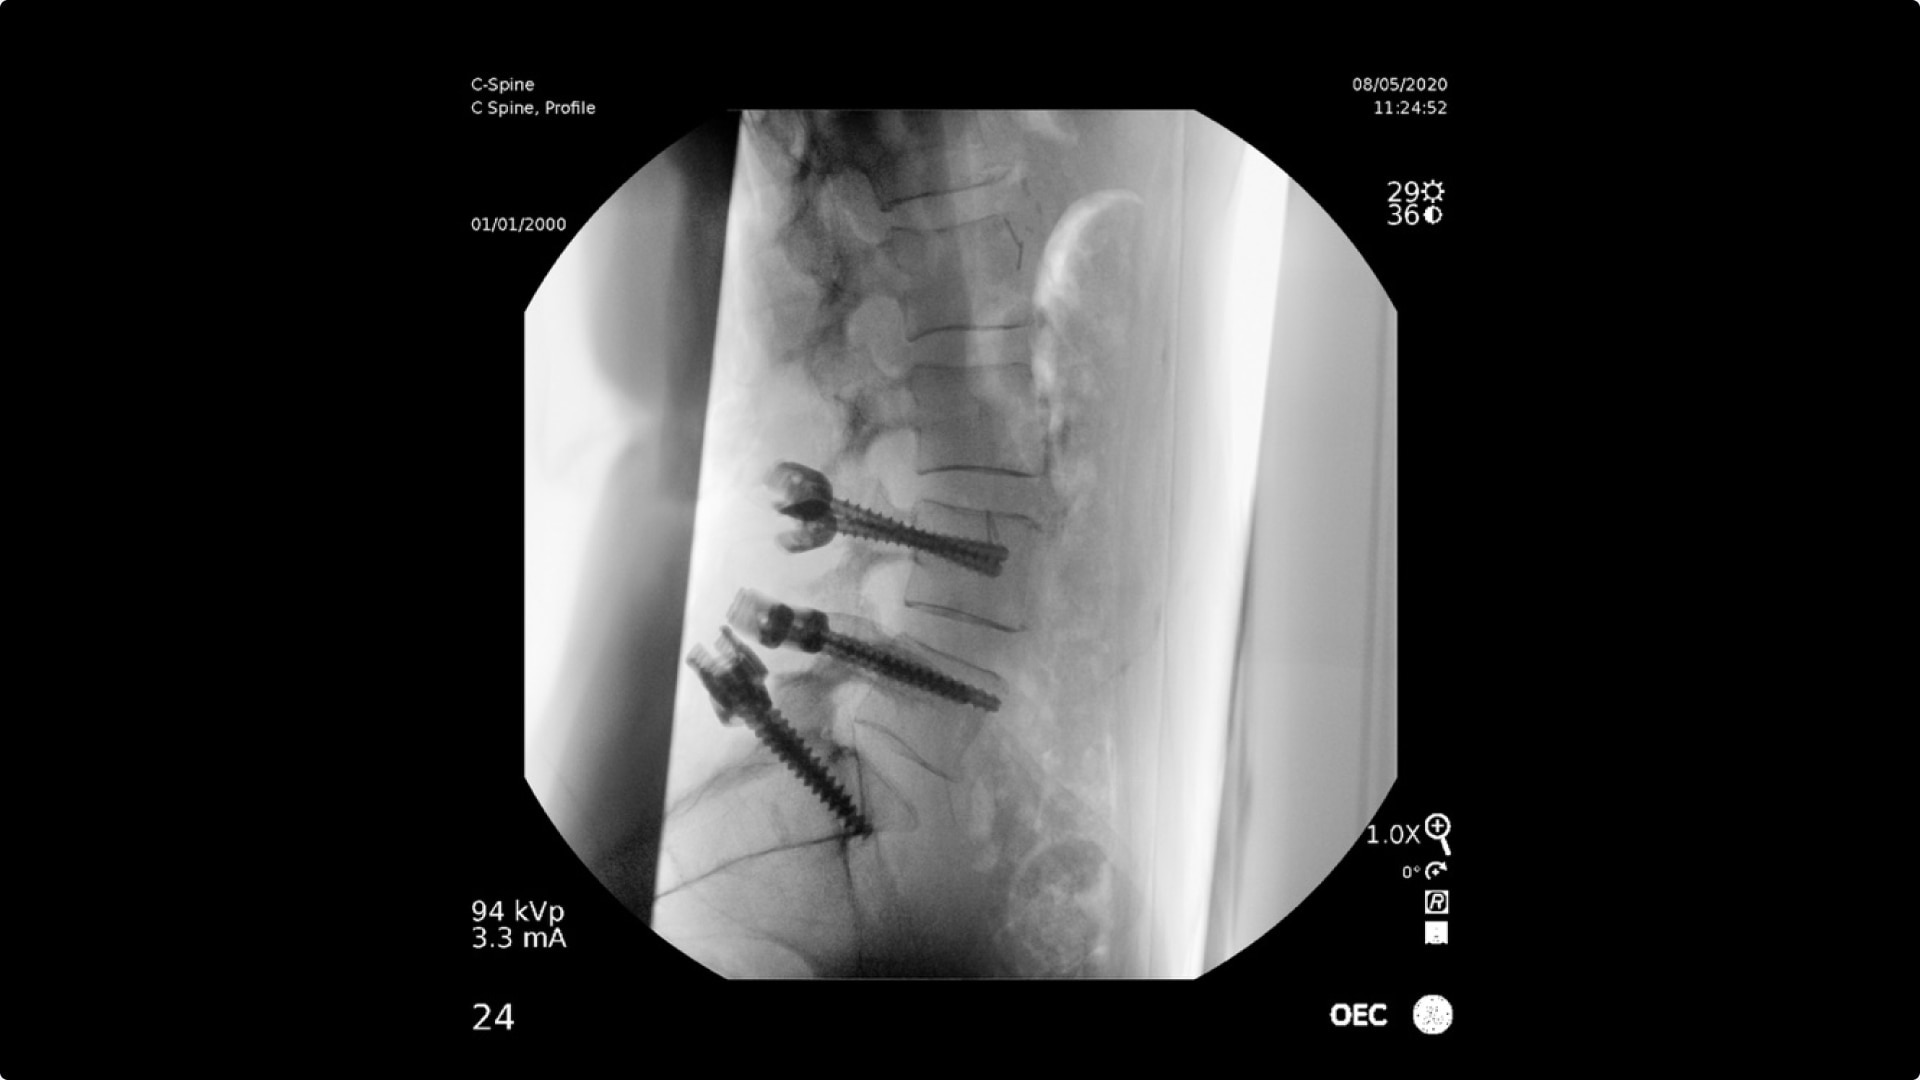

C-arms for Pain Management

Consistently experience amazing image quality, precision, and efficiency during simple to complex pain management procedures with OEC C-arms.

OEC C-arms perform imaging in a variety of procedures such as:

• Steroid injections

• Radiofrequency treatments

• Contrast media injections

• Cervical spine pain management

• Thoracolumbar procedures